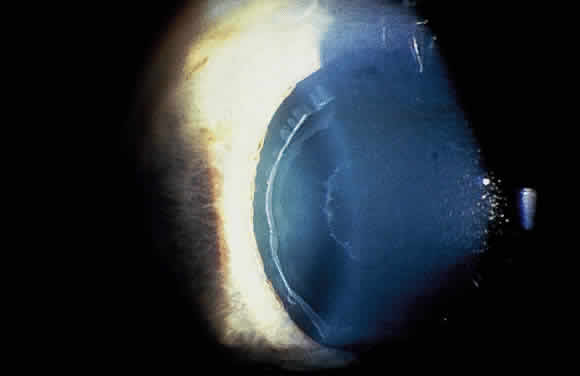

HISTOPATHOLOGY

Accumulation of exfoliative material may be detected histopathologically throughout the anterior segment to include the lens, iris, trabecular structures, conjunctiva, ciliary body, and zonules. The deposition of fibrillar eosinophilic material on the anterior lens capsule is the classic histopathologic feature of XFS (Fig. 9). Ultrastructural studies also indicate some degree of actual exfoliative changes or peeling of the anterior lens capsule74 (Figs. 10 and 11). In addition, Ashton and associates describe a degenerative band containing exfoliative material within the inner half of the lens capsule.5 Bertelsen and coworkers independently noted projection of coarse fibrils from the lens surface into the deep portion of the lens capsule to form an amorphous layer of the lens capsule between the lens epithelium and normal lens capsule.6 Thus, studies indicate that exfoliative material accumulates on the anterior lens surface but also that the lens capsule itself may be involved, and that the underlying epithelial layer may at least partially contribute to the production of the exfoliative material.

Fig. 9. Deposition of fibrillar eosinophilic material on anterior lens capsule in exfoliation syndrome (PAS, × 250). (Courtesy of Dr. Marilyn C. Kincaid and Armed Forces Institute of Pathology, Washington, DC)

Fig. 10. Scanning electron micrograph showing layer of anterior lens capsule and exfoliative material (PC) peeling back from rest of capsule. Asterisks indicate exfoliative vegetations (× 5340). (Dark AJ, Streeten BW, Cornwall CC: Pseudoexfoliative disease of the lens: A study in electron microscopy and histochemistry. Br J Ophthalmol 61:466,1977)